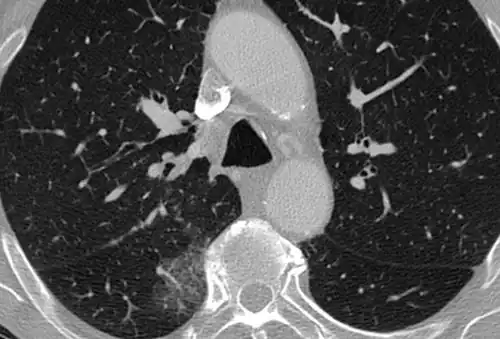

High-Resolution CT image in a patient with Pneumocystis pneumonia infection showing ground-glass opacities.

Inflammation and fibrosis can also cause diffuse GGOs. Pneumocystis pneumonia, an infection typically seen in immunocompromised (e.g. patients with AIDS) or immunosuppressed individuals, is a classic cause of diffuse GGOs. Many viral pneumonias and idiopathic interstitial pneumonias can also lead to a diffuse GGO pattern. Radiation pneumonitis, a side effect of pulmonary radiation therapy, can lead to pulmonary fibrosis and diffuse GGOs.[6]